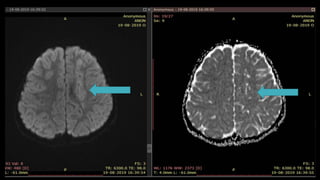

• #42 On DWI ….. ADC value decrease and appears DARK with high signal intensity on DWI

• #46 Here is the example of the same patient shown before. DWI shows hyperintensity in the right frontoparietal region with hypointensity on corresponding ADC map s/o diffusion restriction

• #47 MR 2D ANGIO and 3D TOF MIP images show loss of flow related signals in right MCA. RIGHT ICA appear decreased in calibre as compared to left ICA